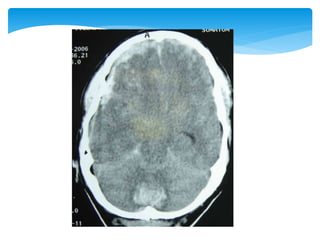

Approach To CTScanCT scan Bone window Look for fractures- •Cranial vault •Skull base •Facial bones Tissue window •EDH •SDH •ICH •Contusions •Pneumocephalus •Hydrocephalus •Cerebral edema Subdural window •Any hemorrhage •Soft tissue and bone •Fontanel •Suture lines •Foreign bodies

 Appearance ofthe normal structures CT Scan